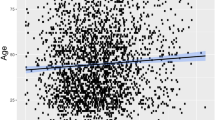

Correlation between Ct Value and Community Prevalence of SARS-CoV-2

All the included studies examined the association between Ct values and epidemiological trends (Table 2). Many retrospectively examined the cross-correlation (lag lead) between Ct values and epidemiological trends. Almost half the studies reported a time lag in the negative cross-correlation between Ct values and new daily cases, with seven studies reporting time lags between 1 and 3 weeks [2, 3, 13, 15, 18, 20, 26], and one study reporting a time lag of 33 days [14] (Table 2). Five studies looked at the correlation between Ct values and the stages of different epidemic waves of SARS-CoV-2 [15,16,17, 21, 23]. These studies found that as case numbers increased towards the peak of an epidemic wave there was an increase in viral loads as determined by low Ct values; towards the end of epidemic waves, there was also a higher proportion of patients with high Ct values, and therefore a decrease in viral load (Table 2).

Lin et al. fitted a log linear regression to the daily Rt, on daily mean and skewness of Ct values at sampling during a training period wave to determine real-time assessment of transmission in the community using Ct values (Table 2). The results from the training model were used to successfully predict real-time estimations of Rt in a subsequent wave [24]. The temporal Ct distribution correlated with the incidence-based Rt over both epidemic waves. Higher values of incidence-based Rt were associated with decreasing average Ct values (Spearman’s correlation coefficient, ρ = −0.79, P < 0.001, and ρ = −0.52, P < 0.001, for the initial and subsequent wave respectively).

Yin et al. found that each epidemic wave was preceded by a drastic decrease in Ct values several days earlier. There was a 17-day time lag in the median Ct value negative correlation with the mean daily positive tests. An extended SEIR-type model found that the Ct values by all ages and age classes was negatively correlated with the estimated daily prevalence in Belgium (Table 2) [20].